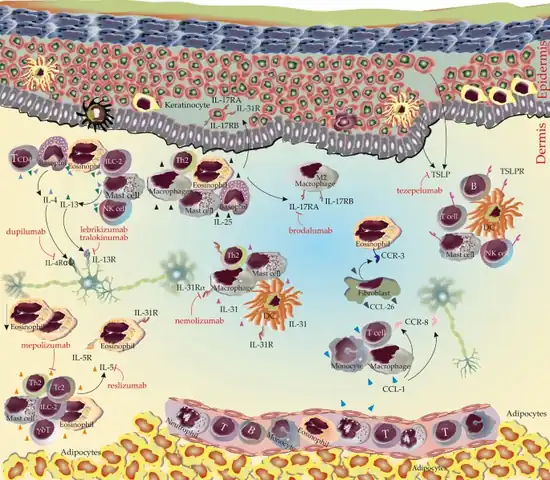

.png.webp)

- ↑ Hu, Man; Scheffel, Jörg; Elieh-Ali-Komi, Daniel; Maurer, Marcus; Hawro, Tomasz; Metz, Martin (1 December 2023). "An update on mechanisms of pruritus and their potential treatment in primary cutaneous T-cell lymphoma". Clinical and Experimental Medicine. 23 (8): 4177–4197. doi:10.1007/s10238-023-01141-x. ISSN 1591-9528.